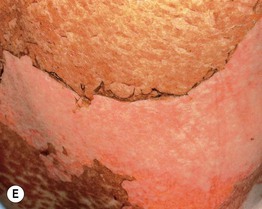

• Clinical staging is based on the proportion of the cutaneous surface involved: Stage 1, <25%; Stage 2, 25–50%; and Stage 3, >50%. Stage 4 represents erythroderma with bullae/epidermal detachment resembling toxic epidermal necrolysis (Fig. 44.1).

Fig. 44.1 Clinical spectrum of acute cutaneous graft-versus-host disease. A Stage 1 – discrete and coalescing small pink papules on the upper chest and neck of a woman 6 weeks following allogeneic bone marrow transplant. B, C Stage 2 – pink macules and papules of the palms that are becoming confluent 14 weeks post allogeneic bone marrow transplant and pink-violet macules and minimally elevated papules on the abdomen in a liver transplant recipient. D Stage 3 – diffuse erythema with desquamation, but without bullae formation. E Stage 4 – coalescence of bullae plus epidermal necrosis leading to large areas of denudation in a patient who had received an allogeneic bone marrow transplant; note the resemblance to toxic epidermal necrolysis. A, D, Courtesy, Edward Cowen, MD; B, Courtesy, Dennis Cooper, MD; C, Courtesy, Julie V. Schaffer, MD.